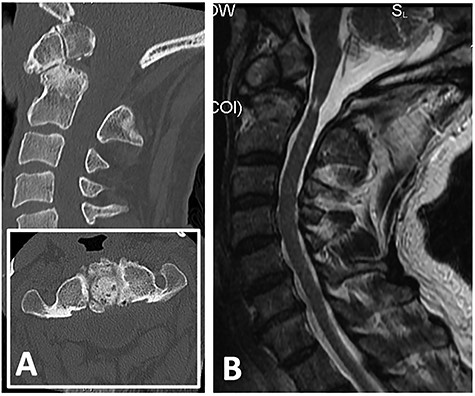

Computed tomography (CT) demonstrated non-union between the odontoid process and body of axis, as well as absence of the posterior arch of atlas (Fig. 1A). Magnetic resonance imaging revealed myelomalacia at the level of non-union likely due to repetitive dynamic compression (Fig. 1B). Flexion–extension X-ray films confirmed significant distraction and forward translation at the atlanto-axial joint (Fig. 2).

Note the absence of posterior arch of atlas (C1); (A) flexion X-ray revealed antero-inferior translation of atlas (C1) on axis (C2); (B) extension X-ray revealed postero-superior translation of atlas (C1) on axis (C2).